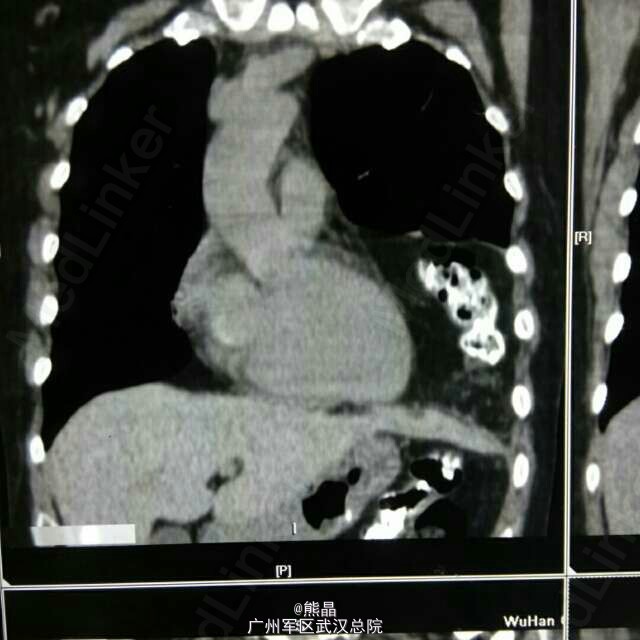

食管憩室术后

食管憩室

此病例为县医院食管憩室手术后病人,来本院做钡餐,钡餐是我做的,高度怀疑膈疝,后做了CT三维确诊。 大家可以看看图,哪里有不明白的可以问我。